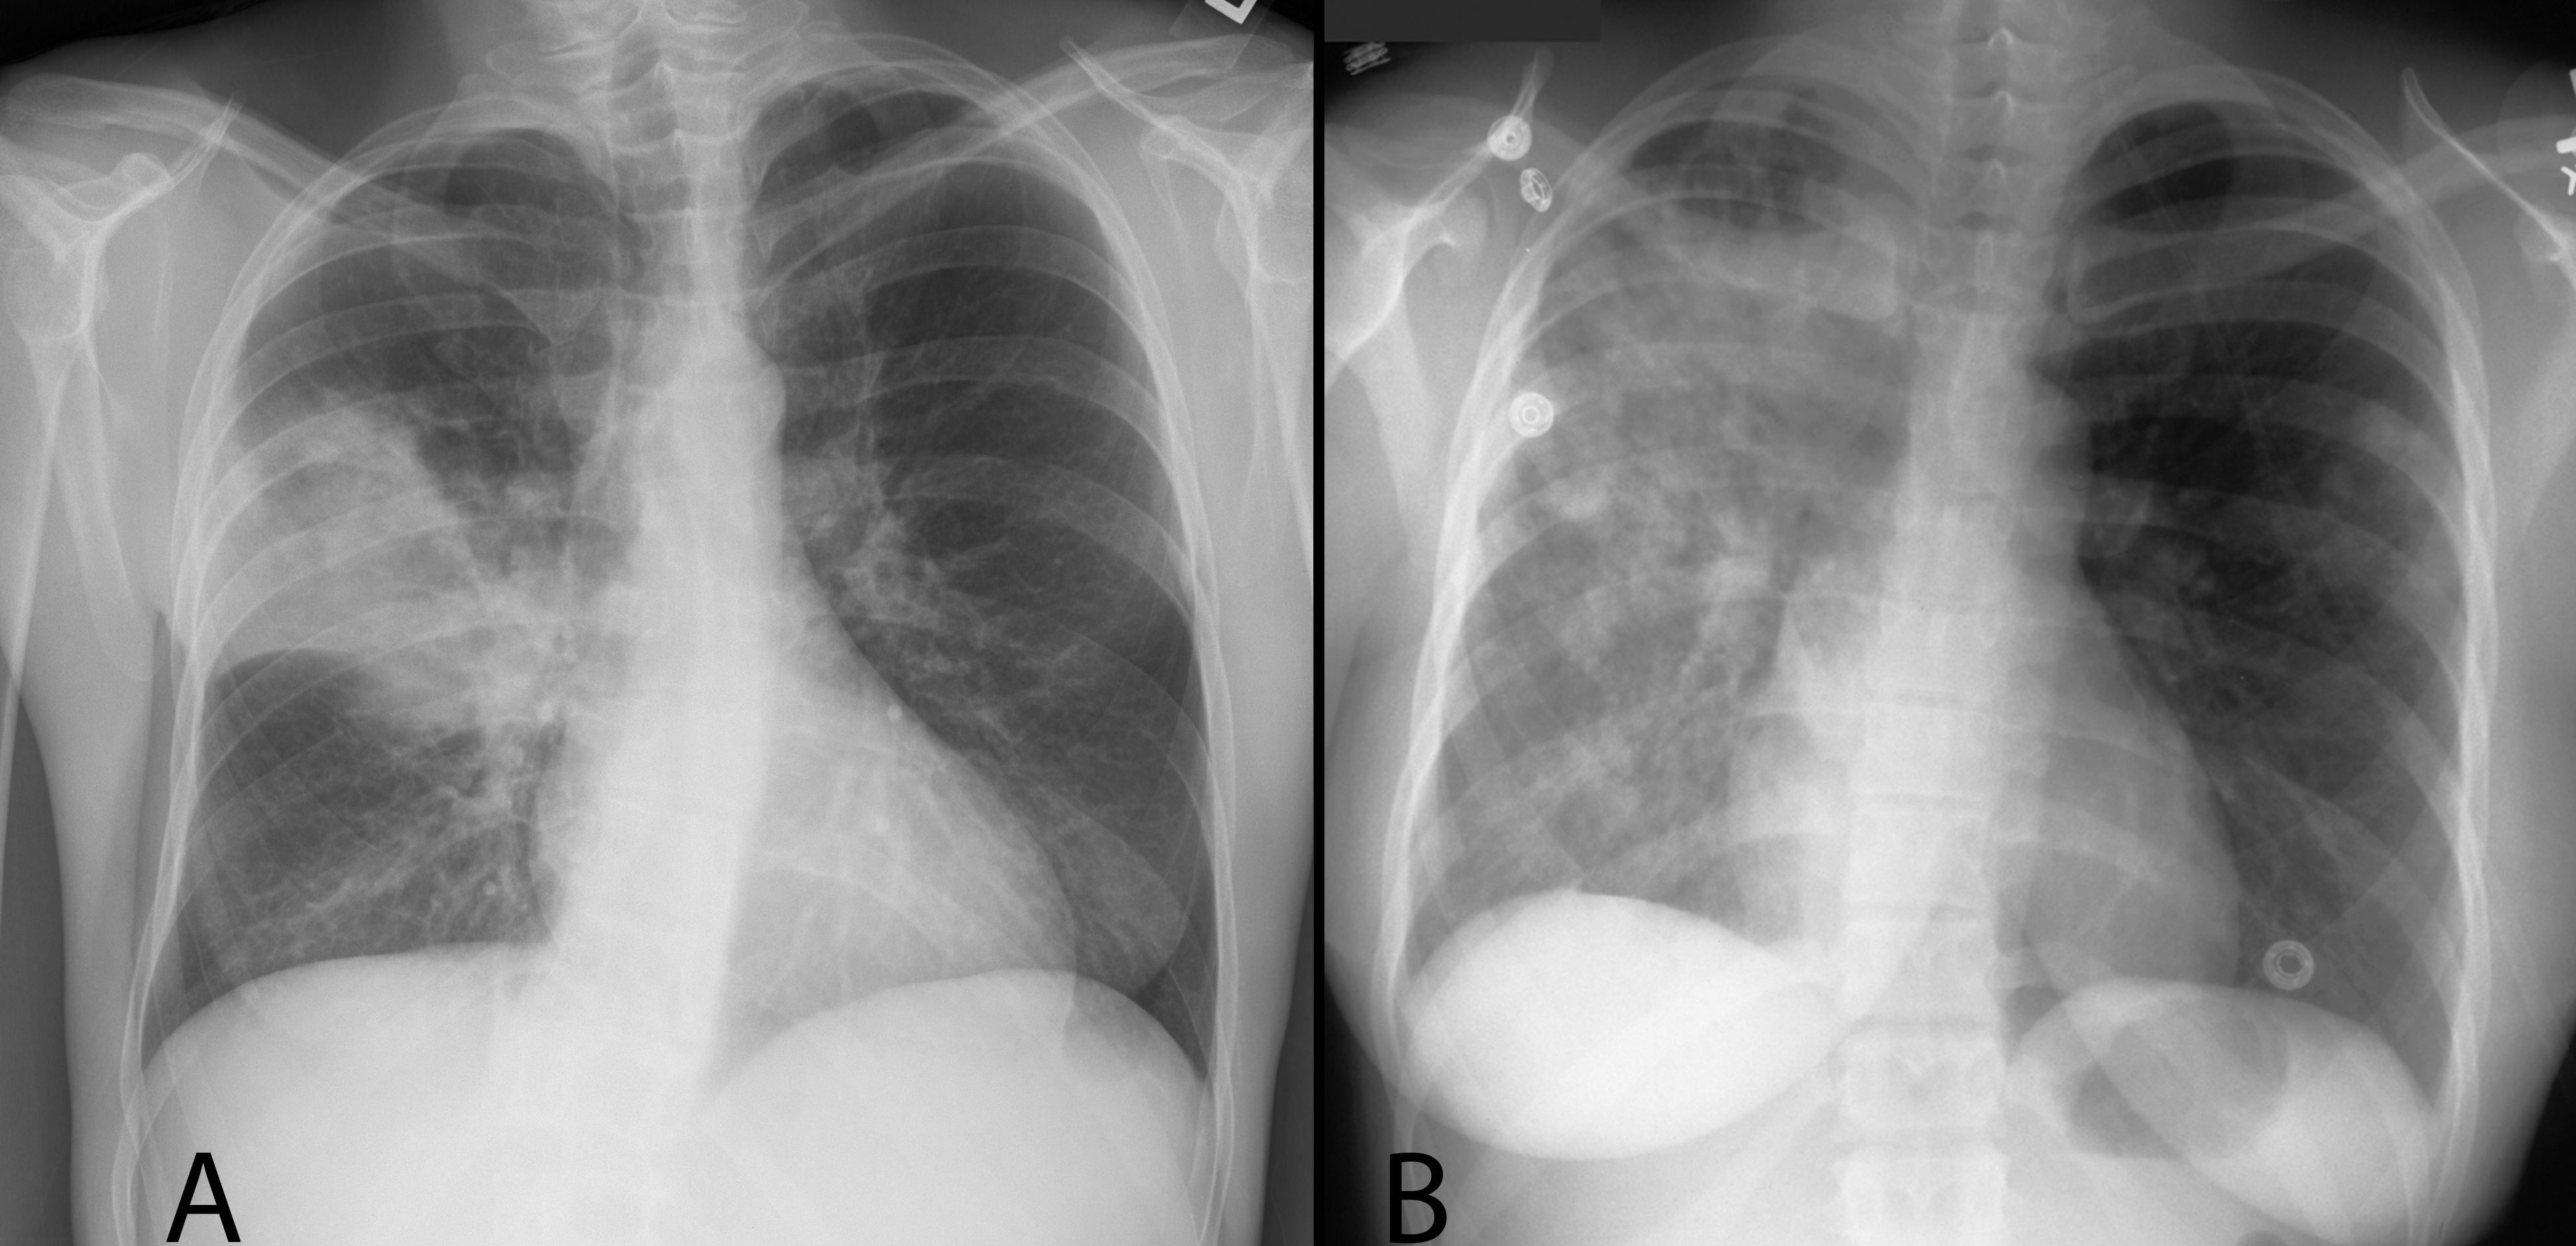

First pair--decide which image shows lung volume loss vs pleural effusion. Realize that BOTH volume loss and effusion cause opacification (whiteness) on the chest radiograph.